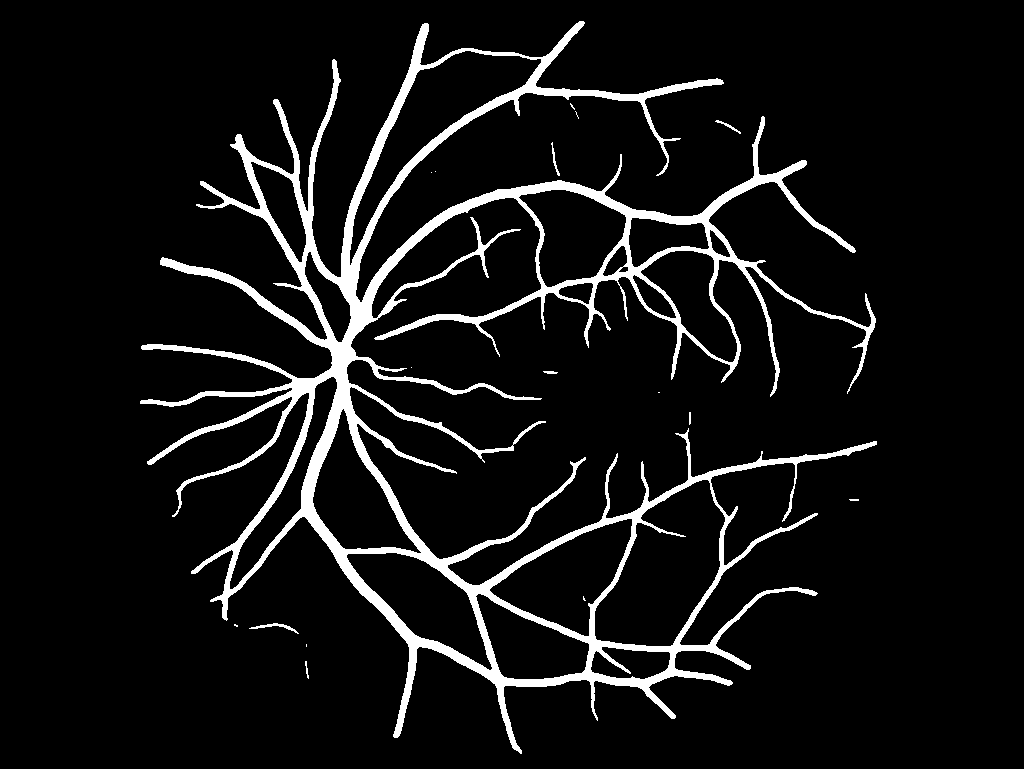

Example Output

Binary vessel segmentation mask

The output visualization provides:

• A binary vessel mask highlighting detected vessels

• Clear separation of vascular structures from background

• Output suitable for quantitative vessel analysis